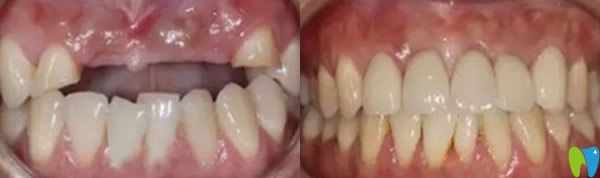

三個(gè)月后,我們又來到成都瑞爾口腔,醫(yī)生說恢復(fù)的很不錯(cuò),牙槽骨和種植體已經(jīng)緊密結(jié)合,可以安裝基臺,戴上牙冠后,牙齒咀嚼功能恢復(fù)了,可承受正常的咀嚼力量,美觀上幾乎和自然牙一樣。郝亦工醫(yī)生建議后期一定要保持好口腔衛(wèi)生健康,細(xì)心呵護(hù),這樣能夠保證種植牙的使用壽命。

在成都瑞爾口腔種植牙技術(shù)解決了老公牙齦萎縮,精神面貌也好了,不再像個(gè)糟老頭,整個(gè)人也精神起來啦!